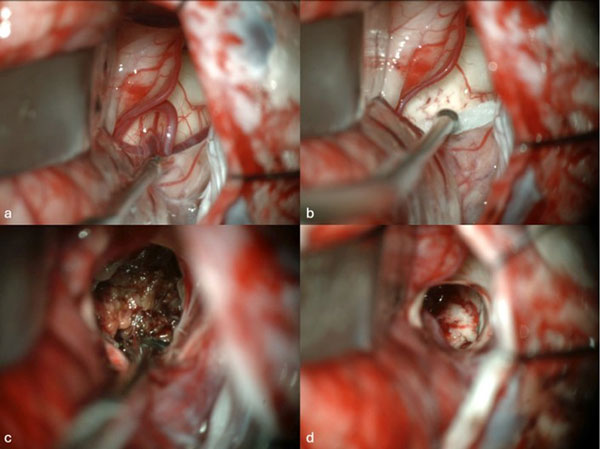

Figura 1. Imágenes intraoperatorias bajo microscopía. Craneotomía suboccipital lateral. Se ingresa al mesencéfalo desde posterior por una ruta supracerebelosa infratentorial lateral. A y B) Corticotomía en surco mesencéfalo lateral. C) Identificación y resección en bloque de la malformación cavernomatosa. D) Revisión del lecho, sin remanente.

Figura 7. Imágenes intraoperatorias bajo microscopía. Abordaje retrosigmoideo ampliado a izquierda, con ruta de ingreso transpedúnculo cerebeloso medio. A) Apertura de fisura horizontal que divide los lóbulos semilunar superior y semilunar inferior del cerebelo, exponiendo el pedúnculo cerebeloso medio. B) Corticotomía en pedúnculo cerebeloso medio, evidenciando la cápsula del cavernoma. C) Resección en bloque de la malformación cavernomatosa. D) Revisión del lecho, sin remanente.